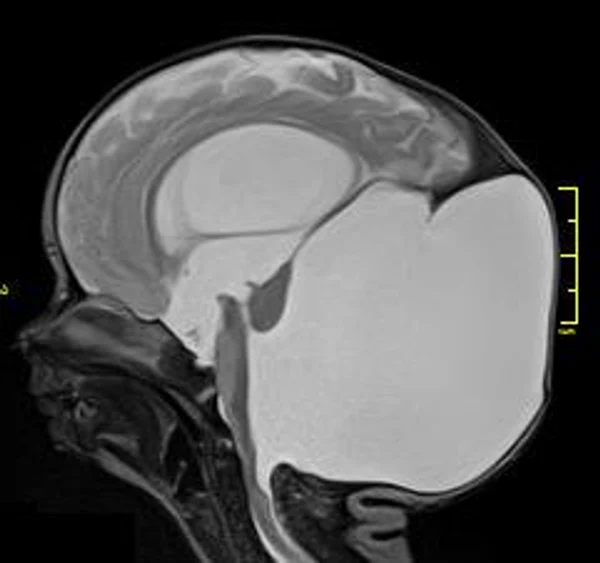

кисты, аномалии Денди-Уокера и др.Операции при внутричерепных кистах. В основном встречаются арахноидальные кисты различных локализаций и кисты сосудистых сплетений боковых желудочков. Пациентам с врождёнными кистами операции проводятся в следующих ситуациях: увеличении объема кисты в динамике, наличии клинических проявлений, компрессии и дислокации мозговых структур, наличии окклюзии ликворных путей. Нами используются 2 способа хирургического лечения кист: эндоскопическая перфорация стенок кист и открытая резекция кист. Открытая резекция кист проводится при ретроцеребеллярных арахноидальных кистах (рис. 2), при арахноидальных кистах межполушарной щели при отсутствии непосредственного контакта их стенок со стенками расширенных желудочков головного мозга и повторного увеличения кист средней черепной ямки после эндоскопической кисто-цистерностомии. Техника операции заключается в проведение краниотомии и максимальном иссечении стенок кист с созданием широкого сообщения кист с субарахноидальным пространством. Эндоскопические операции проводятся при арахноидальных кистах межножковой и пинеальной цистерн, арахноидальных кистах межполушарной щели при тесном контакте их стенок со стенками расширенной желудочковой системы (рис. 3), первично при арахноидальных кистах средней черепной ямки, а также при кистах сосудистых сплетений боковых желудочков. При арахноидальных кистах межножковой цистерны эндоскопически проводится перфорация стенок кисты, сообщая ее с просветом III желудочка и межножковой цистерной – эндоскопическая вентрикуло-кисто-цистерностомия (рис. 4). При арахноидальных кистах пинеальной цистерны проводится перфорация кисты в передне-верхних её отделах с созданием сообщения полости кисты с просветом III желудочка – эндоскопическая кисто-вентрикулостомия. С целью предотвращения облитерации сформированного отверстия иногда в полость кисты под контролем эндоскопа вводится стент перфорированный на протяжении (рис. 5, 6). Эндоскопическая кисто-цистерностомия выполняется при арахноидальных кистах средней черепной ямки. При этом создается широкое сообщение кисты с базальными цистернами. При кистах сосудистых сплетений боковых желудочков проводится их вскрытие в просвет боковых желудочков – эндоскопическая кисто-вентрикулостомия. При множественных кистах проводится их хирургическое сообщение между собой – интеркистосмия